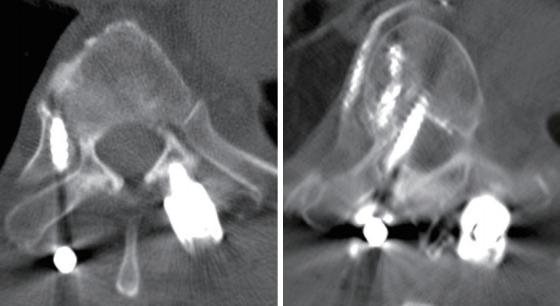

A retrospective review of adult patients who underwent pedicle screw fixation in the thoracic or lumbar spine for metastatic spinal tumors between 2012 and 2018 was conducted. Breaches were assessed based on the Gertzbein and Robbins classification and only screws placed >4 mm outside of the pedicle wall (lateral or medial) were considered breached.

A total of 62 patients received 547 pedicle screws (average 8 per patient) - 34 patients received 298 pedicle screws in the FH group and 28 patients received 249 screws in the NV group. There were 40/547 breaches, corresponding to a breach and accuracy rate of 7.3% and 92.7%, respectively. The breach rate was 9.7% in the FH group and 4.4% in the NV group (chi-squared test, p=0.017); this corresponded to an accuracy rate of 90.3% and 95.6%, respectively. Only one patient from the overall cohort (in the FH group) required revision surgery due to a medial breach abutting the spinal cord (1.6% of all patients; 2.9% of FH patients); no patient suffered organ, vessel, or neurological injury from screw breaches.

Navigated pedicle screw placement in patients with metastatic spinal tumors has a significantly higher radiographic accuracy compared to the FH technique. However, the revision surgery was low and no patient suffered from clinically-relevant breach. Navigation also offers the advantage of real-time localization of spinal tumors and aids in targeting and resection of these lesions.

对2012年至2018年间因转移性脊柱肿瘤在胸腰椎接受椎弓根螺钉固定的成年患者进行回顾性研究。根据Gertzbein和Robbins分类评估穿破情况,仅将置入椎弓根壁外侧或内侧超过4 mm的螺钉视为穿破。

共有62例患者接受了547枚椎弓根螺钉(平均每位患者8枚)——FH组34例患者接受了298枚椎弓根螺钉,NV组28例患者接受了249枚螺钉。547枚螺钉中有40枚穿破,穿破率和准确率分别为7.3%和92.7%。FH组穿破率为9.7%,NV组为4.4%(卡方检验,p = 0.017);相应的准确率分别为90.3%和95.6%。整个队列中只有1例患者(FH组)因靠近脊髓的内侧穿破需要翻修手术(占所有患者的1.6%;占FH组患者的2.9%);没有患者因螺钉穿破而遭受器官、血管或神经损伤。

与FH技术相比,转移性脊柱肿瘤患者采用导航椎弓根螺钉置入的影像学准确性显著更高。然而,翻修手术率较低,且没有患者出现临床相关穿破。导航还具有实时定位脊柱肿瘤的优势,并有助于这些病变的靶向和切除。